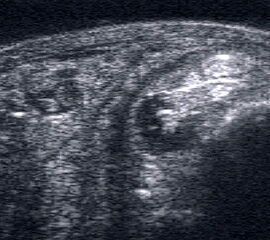

Fibulaverletzung beim Kind

Abgehobenes Periost mit periostalem Hämatom (rechts) mit Gegenseite (links). Die Kortikalis wird unterbrochen von der noch offenen Wachstumsfuge der Fibula.

Abbildung 12

Lagerung: Rückenlage, leichte Innrotation des Fußes.

Schnittebene: LS über distaler Fibula.

Referenzstruktur: Fibula im Längsverlauf.

Befunde: Bei Kindern wird nach Distorsion des OSG mitunter eine Lösung der Fibulafuge vermutet, die jedoch in der klinischen Praxis sehr selten ist. Die seitenvergleichende Untersuchung zeigt dann ein aufgrund des dicken und bei Kindern gut abgrenzbaren echogenen Periosts ein periostales Hämatom, was aber auch ein Hinweis auf eine Fissur oder Fraktur sein kann (Abb.12).